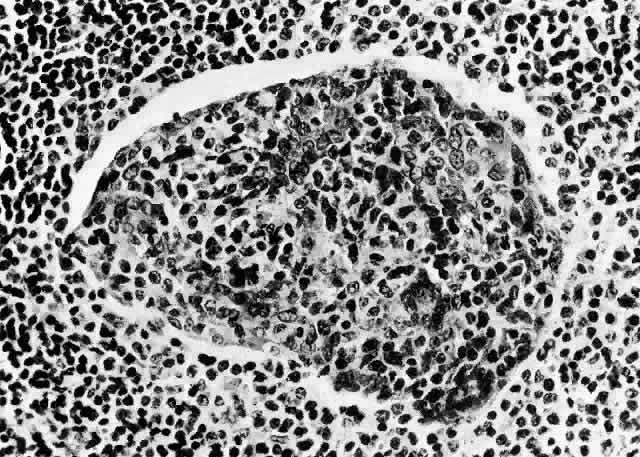

In general, idiopathic orbital inflammation is polymorphic (Figs. 5 AND 6).3,6,7,33,87,88 The cellular response seen in this disease consists of lymphocytes, plasma cells, macrophages, histiocytes, occasional neutrophils and eosinophils, epithelioid cells, and fibroblasts. These are present in varying numbers, depending on the chronicity of the inflammatory process. Intranuclear Dutcher bodies and intracytoplasmic Russell bodies may be present within many of the plasma cells since they actively participate in the inflammatory response. Children tend to have a significant number of eosinophils in their biopsy specimen. Lipogranulomatous inflammation with fat necrosis may also be present. However, the presence of noncaseating granulomas is relatively uncommon.89 This is often associated with foreign body giant cells that are responding to the release of lipid. Perivascular lymphocytic cuffing and capillary proliferation are quite common.3 Occasionally, lymphoid follicles may also be seen.

Fig. 6. Histopathologic sections demonstrating the various pathologic findings associated with idiopathic orbital inflammation. Most commonly these include lymphoid follicles, granulomas, collagen deposition, and a diffuse mixed inflammatory cell infiltrate. The normal tissue architecture is frequently disrupted by these changes. A. Many lymphoid follicles are scattered throughout orbital tissue (H&E, × 63). B. Cells of follicular center are lighter and larger than mantle of mature lymphocytes that surround the germinal zone (H&E, ×160). C. Lacrimal gland elements have undergone atrophy in advanced example of idiopathic dacryoadenitis. Fibrosis and lymphocytes have replaced a considerable amount of gland parenchyma (H&E, ×94). D. Myositis in which lymphocytes are loosely aggregated below center and infiltrate between extraocular muscle fibers (H&E, ×160). E. Cuffing of small vessels by mature lymphocytes. Note loose edematous interstitium between disrupted muscle fibers (H&E, ×240). F. Progressive fibrosis of retrobulbar fat (H&E, ×25).